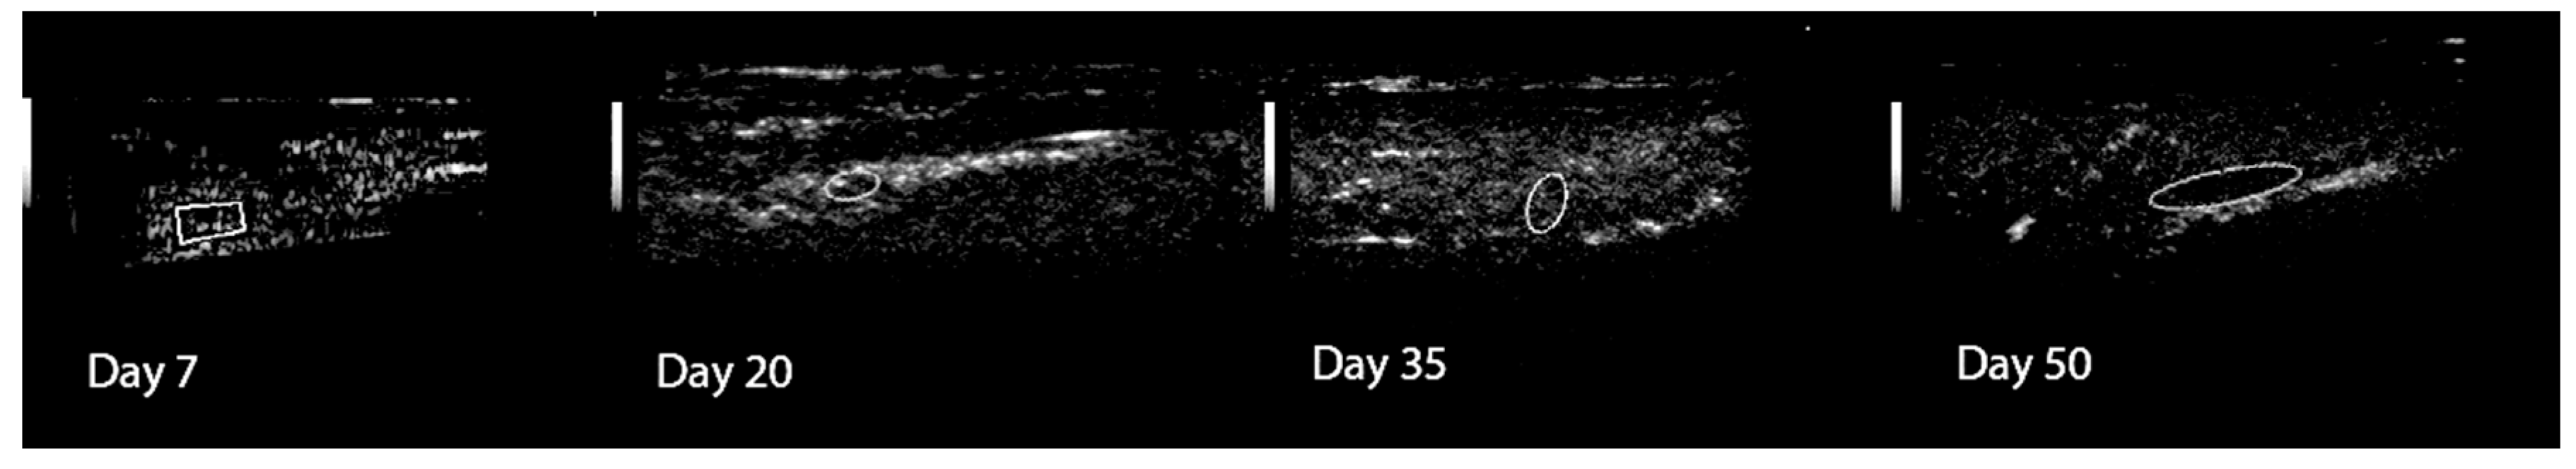

The ultrasound study performed at T7 showed a discontinuity of the bone surface in the fracture gap that was filled with homogeneous hypoechoic to anechoic areas, due to the hematoma formation around the fracture gap. No Doppler signal was visible.

At T20 the ultrasound examination showed uneven and rounded fracture borders due to bone resorption; the soft tissue was heterogeneous and represented the mature hematoma. Poor number of Doppler signals were visible.

At T35 B-mode ultrasound showed the presence of hyperchoic, regular, and homogeneous fibro-cartilaginous tissue into the fracture site due to formation of the callus; the fracture lines were almost completely disappeared. An increase of the number of signals was visible at the callus surface. Finally, the ultrasound examination at T50 showed a thin continuous line of the periosteal bone, demonstrating the successful calcification with the absence of newly formed tissue around the bone. The Doppler examination hardly revealed a very low number of vessel signals (Figure 2).

Doppler ultrasonography of the tibial bone healing: an increase in the number of vascular signals was seen at days 35, after which the vascularization decreased gradually.